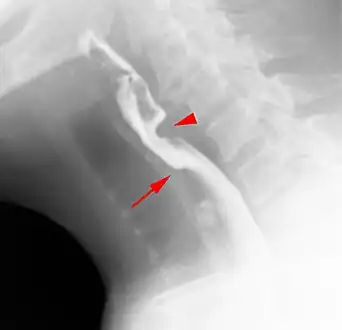

Esophageal webs are thin 2–3 mm (0.08–0.12 in) membranes of normal esophageal tissue consisting of mucosa and submucosa that can partially protrude/obstruct the esophagus. They can be congenital or acquired. Congenital webs commonly appear in the middle and inferior third of the esophagus, and they are more likely to be circumferential with a central or eccentric orifice. Acquired webs are much more common than congenital webs and typically appear in the cervical area (postcricoid).

Clinical symptoms of this condition are selective (solid more than liquids) dysphagia, thoracic pain, nasopharyngeal reflux, aspiration, perforation and food impaction (the last two are very rare).

The diagnostic test of choice is a barium swallow.